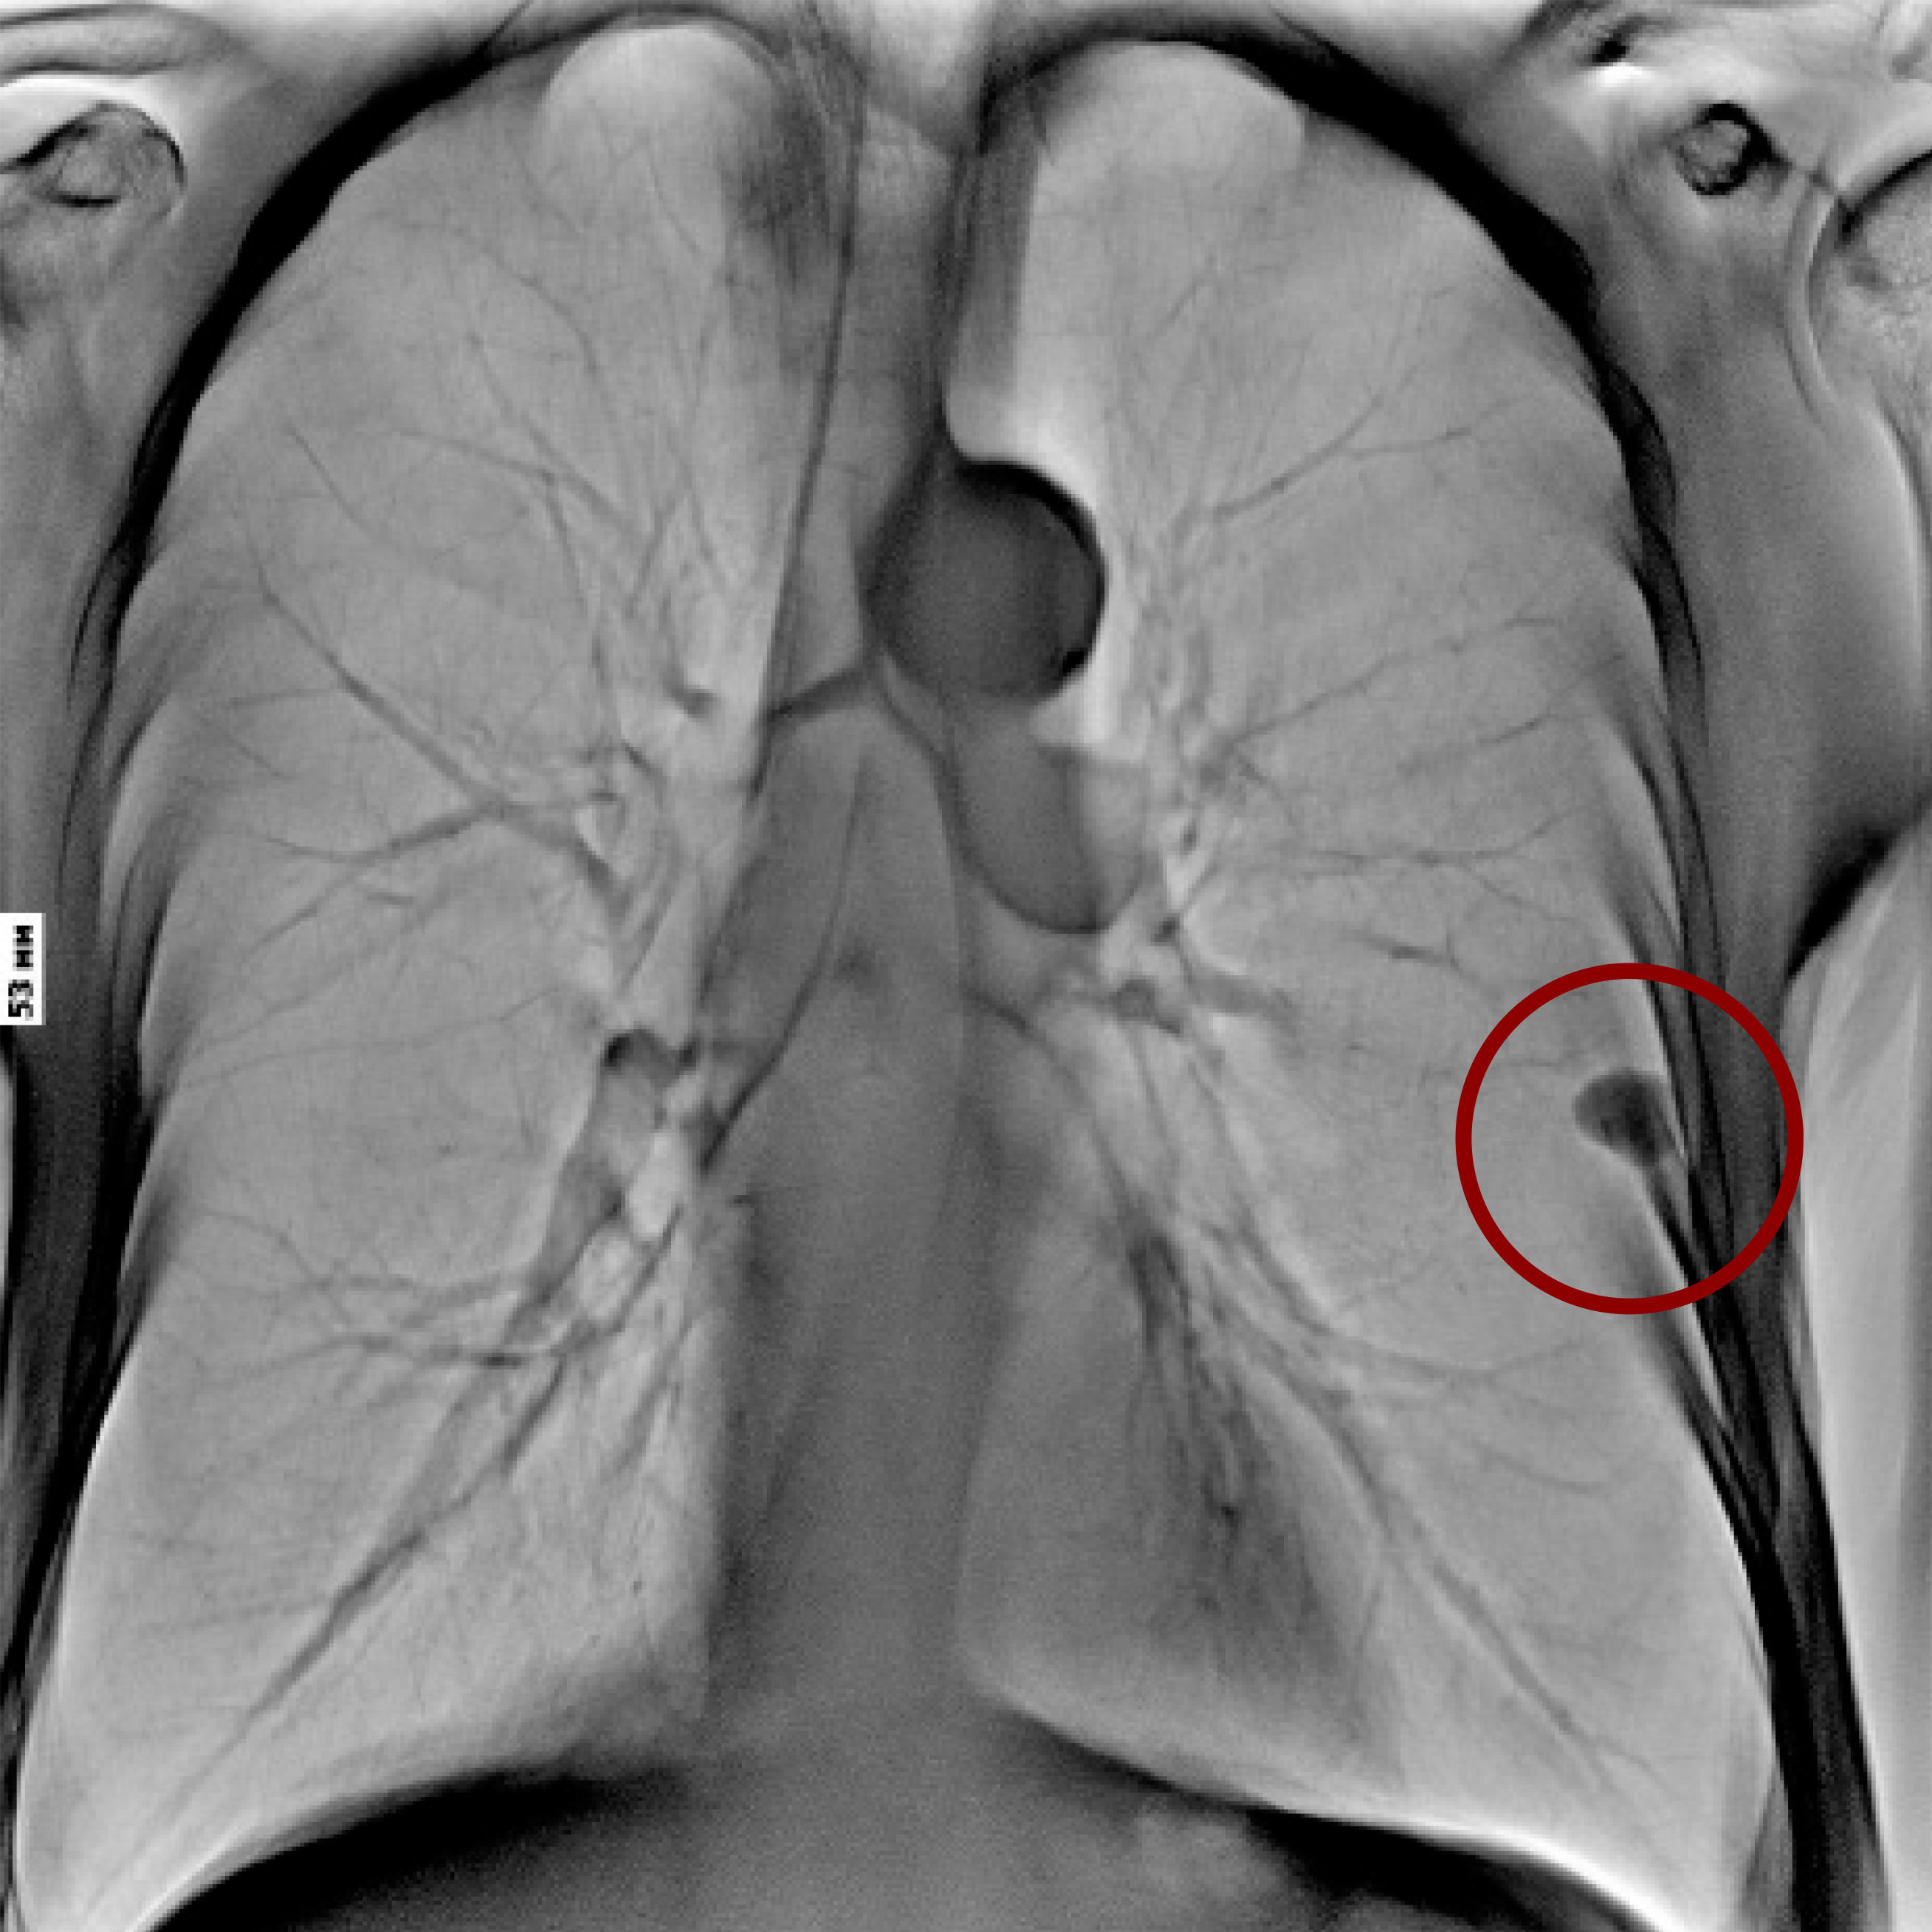

- Различные режимы съемки: рентгенография, рентгеноскопия, линейная томография, томосинтез, сшивка